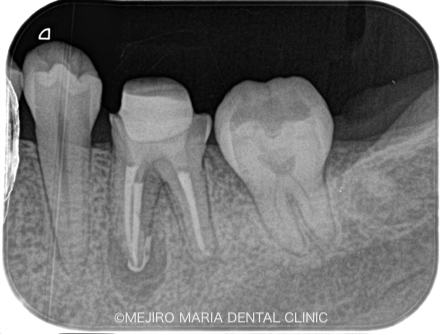

患者様は、数年前にひどい虫歯のために根管治療を受けておられましたが、数日前より左下が腫れ始め、瘻孔(フィステル/溜まった膿を排出する穴)ができたと来院されました。

レントゲンで診査すると、左下6番(第一大臼歯)の近心根(歯の根のより中心に近い部分)に根尖性歯周炎が確認でき、腫脹の原因は根尖性歯周炎であると診断しました。

また、同じ部位の根尖に、透過性の異なる充填物(赤丸)が確認できました。これは、以前の根管治療で使用していた器具が根管内で折れて、そのまま取り残されている状態です。

このように、治療中に折れた器具のことを歯科では「破折ファイル」と言い、トラブルケースの1つとして扱われます。このように細く長い根管で破折したファイルは、再治療の際に根管を洗浄するための器具の到達を困難にし、また、破折ファイルを除去するための器具のアプローチも難しいため、結果として根尖部の洗浄が不十分になってしまいます。